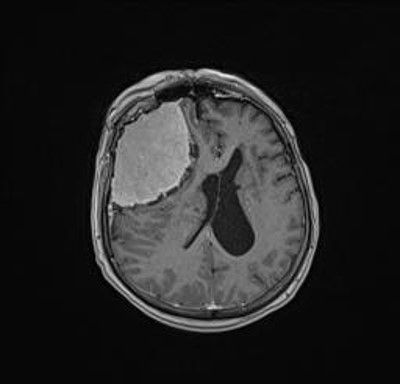

Postoperative MRI after total tumor removal.